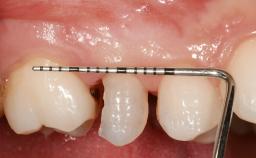

Early Placement of an Implant in a Maxillary Right Central Incisor Site

This 41-year-old female patient was referred to the clinic for the replacement of the right central incisor, since the tooth had developed a root fracture in the long axis that made extraction necessary. The healthy, non-smoking patient was first seen with the tooth still in place. A detailed Esthetic Risk Assessment was performed.The patient was worried about her dental esthetics and had high expectations for a successful treatment outcome from an esthetic point of view. The patient had a medium lip line that displayed parts of the gingiva in the anterior maxilla upon smile.

Prosthesis Type FDP

Mesio-Distal Space Symmetry +/- 1 mm of contra-lateral tooth